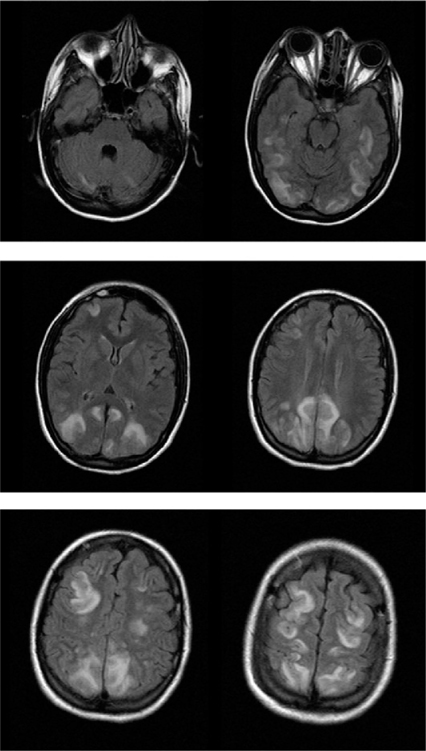

Posterior reversible encephalopathy syndrome (PRES) [1], [2] is a clinicoradiological entity that was well described by Hinchey et al. [3] in 1996 based on 15 cases, shortly after two other small case-series were published [4], [5]. This condition has been designated by a variety of names (reversible posterior leukoencephalopathy syndrome, reversible posterior cerebral edema syndrome, and reversible occipital parietal encephalopathy). PRES is now the accepted term [1], [2], [6] but has been challenged recently based on the risk of neurological impairment and up to 15 % mortality rate [7], [8]. PRES is characterized by variable associations of seizure activity, consciousness impairment, headaches, visual abnormalities, nausea/vomiting, and focal neurological signs. The cerebral imaging abnormalities are often symmetric and predominate in the posterior white matter (Fig. 1). Recognition of PRES has evolved with increasing availability of magnetic resonance imaging (MRI).

Fig. 1

Cerebral magnetic resonance imaging in a patient with posterior reversible encephalopathy syndrome (PRES). Fluid-attenuated inversion recovery (FLAIR) sequence showing bilateral high-signal foci in the cerebellum, basal ganglia, and occipital, parietal, frontal, and temporal lobes